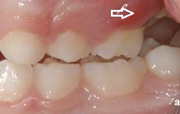

Sümptomid:

- valehambumus (18)